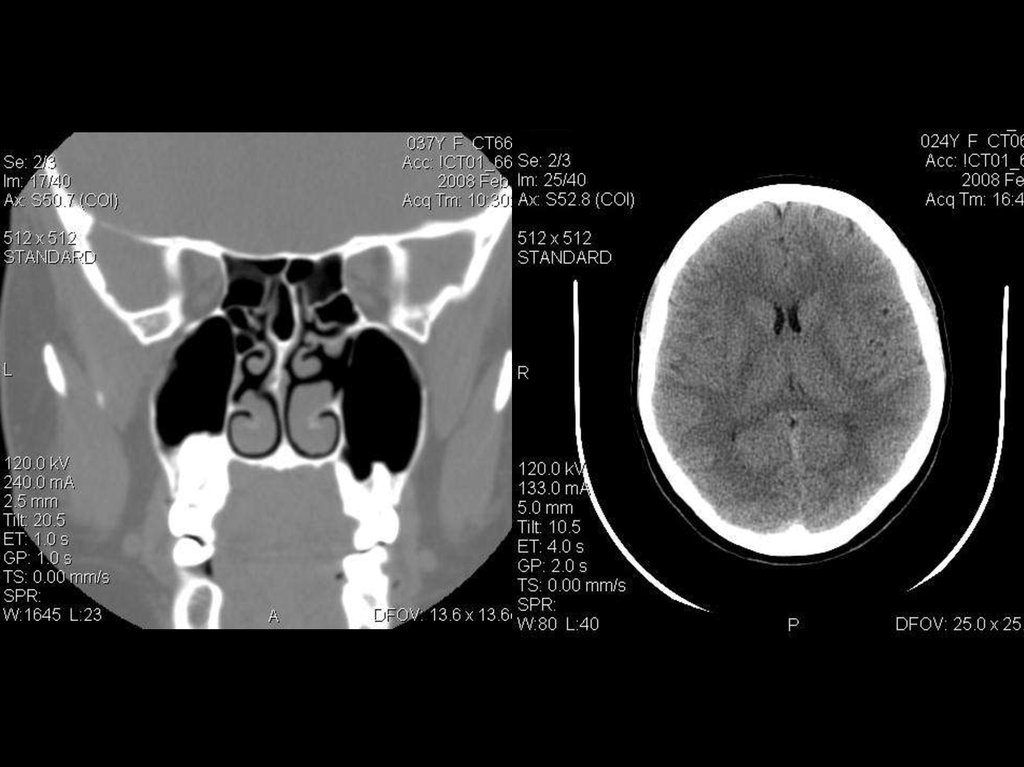

исследование пазух

Ток: 240 мА

Напряжение: 120кВ

Толщина среза: 2.5 мм

Матрица: 512х512

Режим: пошаговый

исследование головного мозга